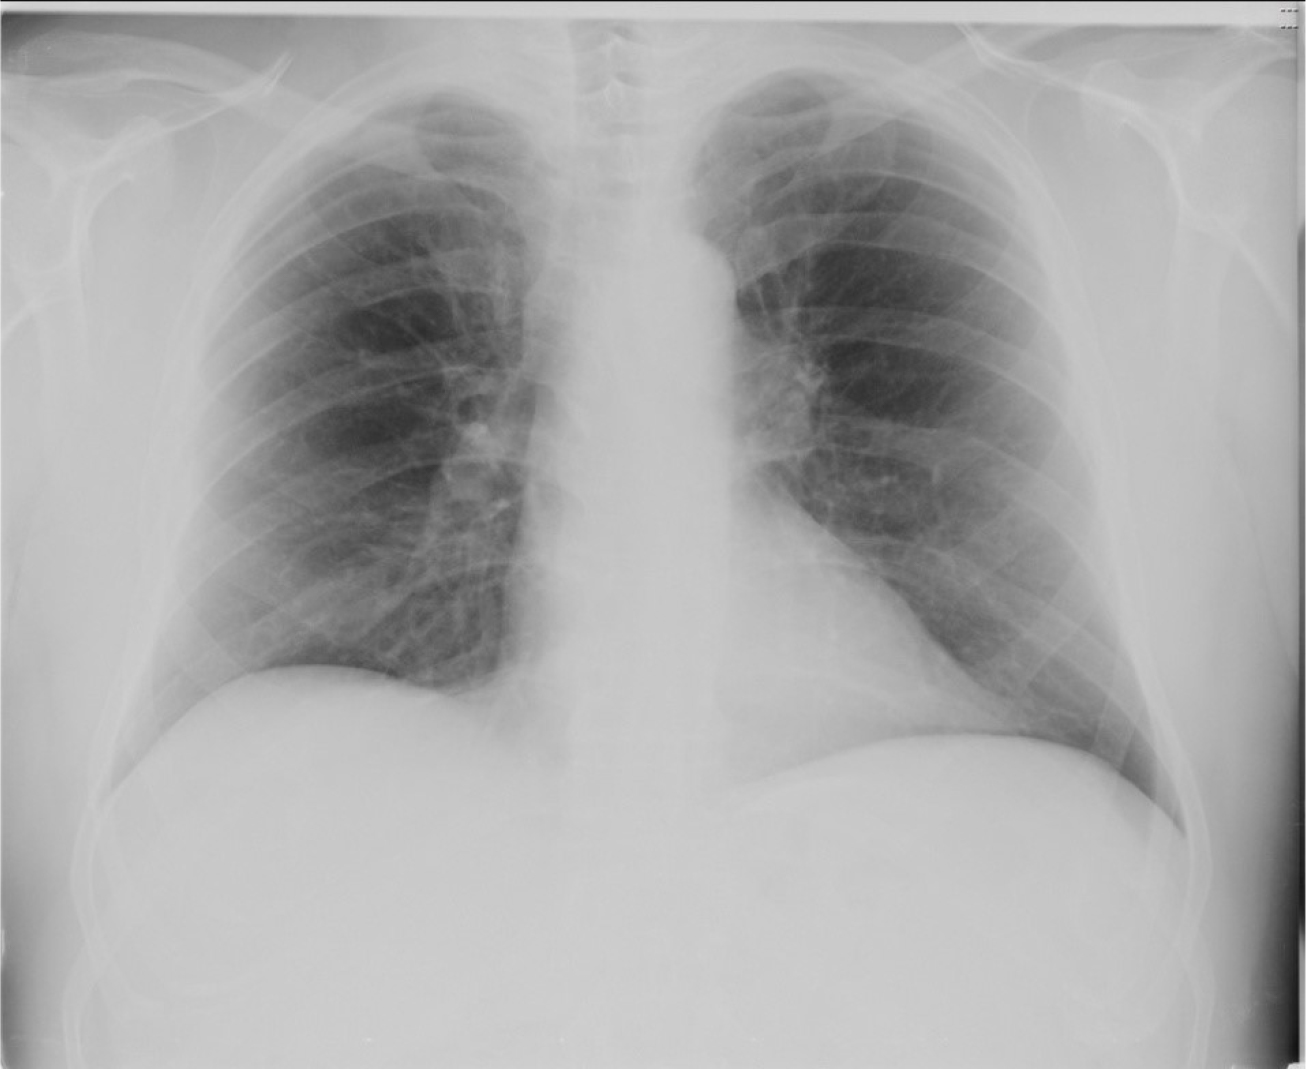

Chest X-Ray in SARS-CoV-2. Chest X-Ray displays a typical bilateral ground glass pattern, which tends to affect the posterior segments of lower lobes, with a peripheral and sub-pleural distribution